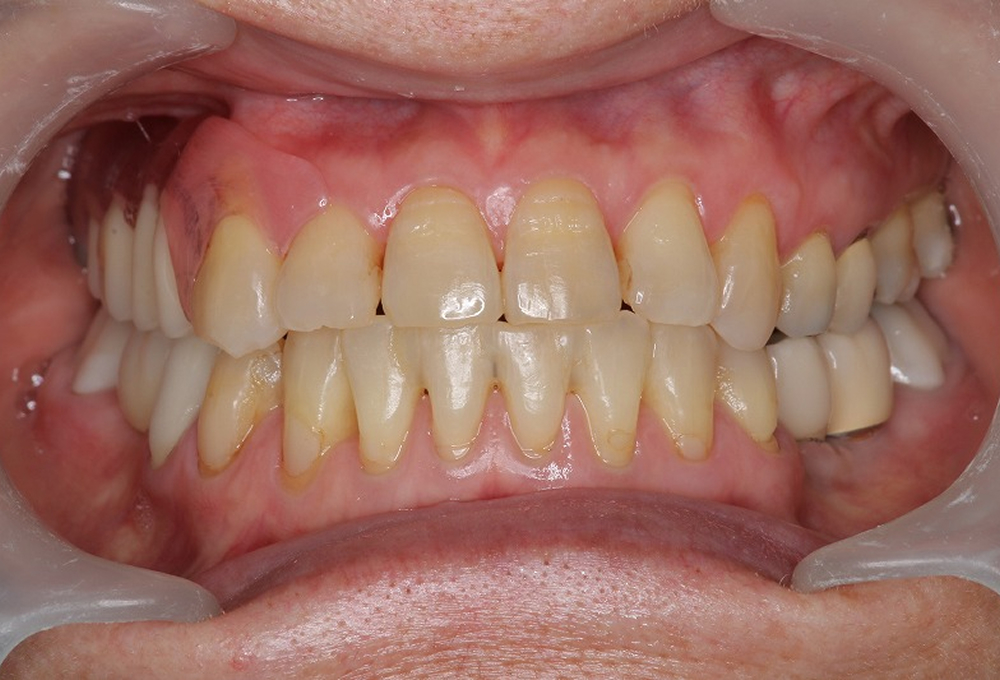

⑨術後

⑦術後